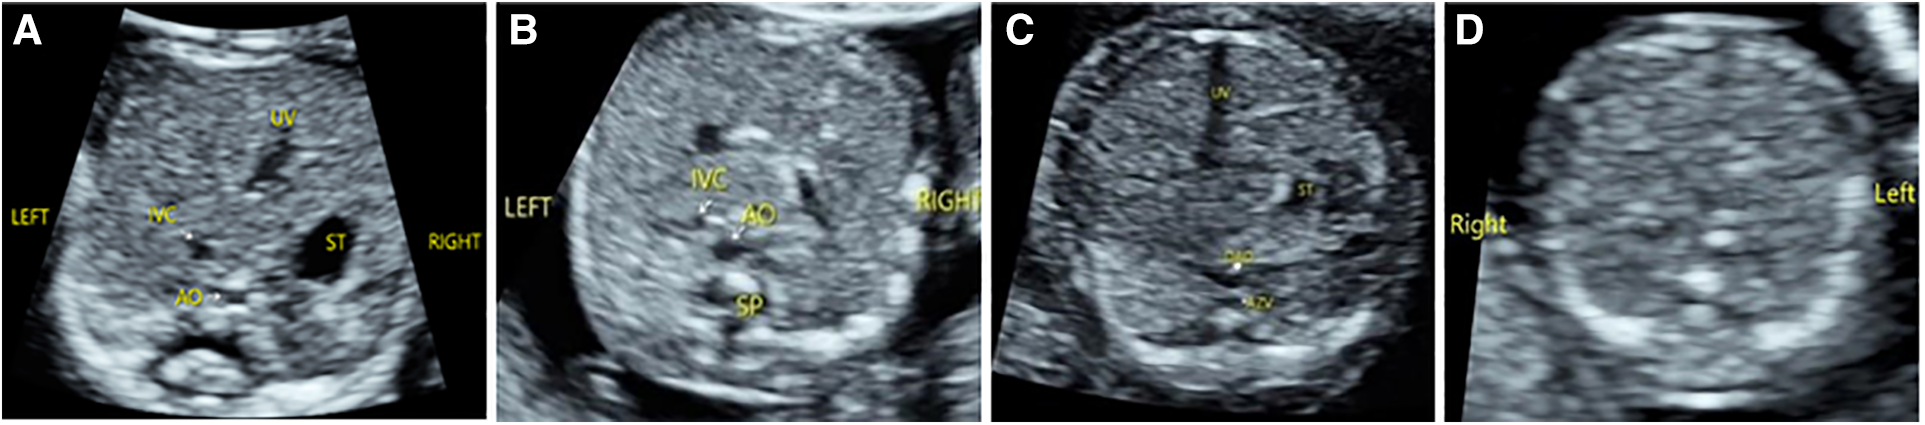

Among the 176 fetuses with CHD, 10 fetuses had an abnormal upper abdominal transverse section. According to the integrity of the fetal abdominal wall and the spatial position of four U-shaped structures (gastric bleb, inferior vena cava, aorta, and spine), four abnormal image patterns of UAb transverse section were found, which could be seen in normal cases, situs inversus, left isomerism syndrome, and right isomerism syndrome (Figure 4). According to the location, size, cardiac axis, the central crisscross structure of the heart and the size and direction of blood flow bundles, 16 kinds of 4CV section abnormal patterns were found (Figure 5). According to the number of large arteries, the relationship between the pulmonary artery and the aorta, the diameter of the pulmonary artery and the aorta, and the direction of blood flow between the ductus arteriosus and the aortic arch, eight abnormal patterns of 3VT section were found (Figure 6). According to the course of bilateral subclavian arteries, two abnormal patterns of BSa sections were found (Figure 7).

Figure 4

Abnormal image pattern of ultrasound in the upper abdominal transverse section. (A) Patterns of UAb-1: The stomach is on the right side of the abdomen, the superior vena cava is on the left front of the spine, and the abdominal aorta is on the right front of the spine. (B) Patterns of UAb-2: The stomach is small and located near the midline, while the superior vena cava is on the same side of the spine as the abdominal aorta. (C) Patterns of UAb-3: The stomach is small and located near the midline, and the dilated (hemiazygos vein) azygos vein is seen behind the right (left) of the descending aorta. (D) Patterns of UAb-4: The stomach is not seen on the transverse section of the upper abdomen.